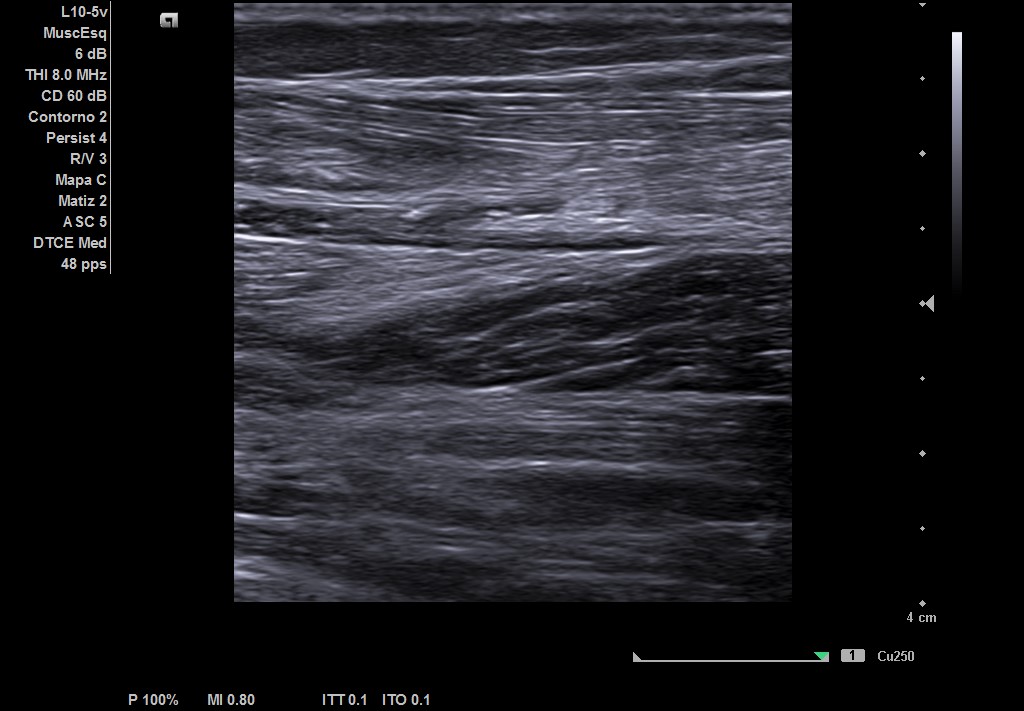

Objetivamos dolor a punta de dedo en zona del gemelo izquierdo con contractura asociada, no otras alteraciones en el resto de explotación de MII. Ante la sospecha de rotura fibrilar, realizamos ecografía.

Descripción de los hallazgos ecográficos y las imágenes más relevantes para la resolución del caso

Ecografía musculoesqueletica: se objetiva signos de rotura de inserción gemeral interno-soleo de 21 x 32 mm y línea de líquido en zona superior intergastronemios de 1 mm de grosor. Doppler negativo.